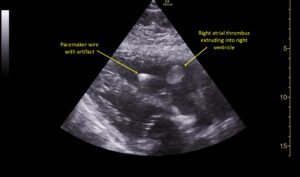

Wolff A, et al. Right atrial thrombosis. Parasternal long US 1, annotated

Wolff A et al. Right atrial thrombosis. Parasternal long US 1 annotated